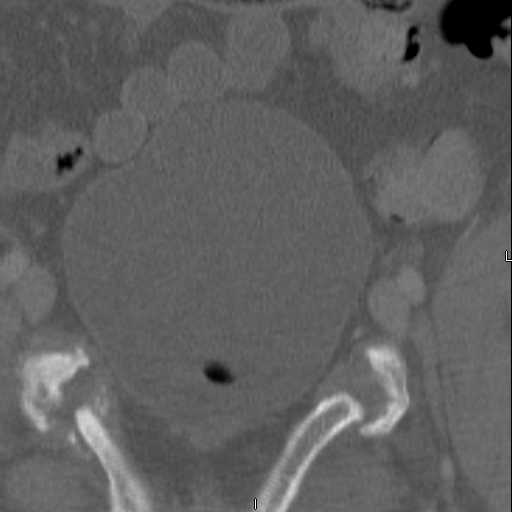

Here are a recent patient’s example slides...

Pelvic CT Scan - 3 Months After Fall

Sacral Injuries

Ramus Fractures

Percutaneous Fixation

(B) Ramus-Retrograde

2 TransIliac-TransSacral

Upper Segment